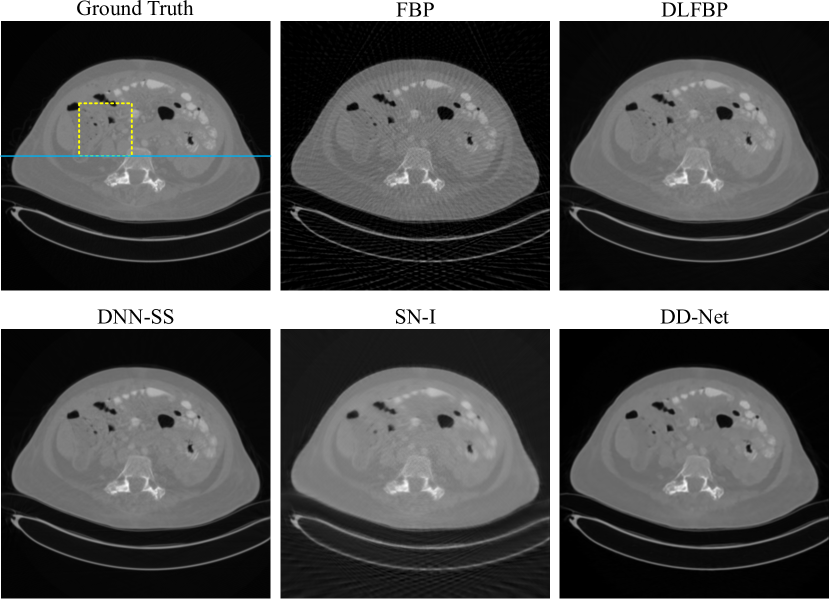

Figs.4-6 present results of one of the 100 synthetic phantoms with 120 views for testing using different methods. Same regions indicated with yellow box are enlarged for better visualization in Fig.5. The image intensity profile in same position is shown in Fig.6.

As expected, severe artifacts exist in the result using FBP, and DLFBP, DNN-SS, SN-I and DD-Net could reduce the artifacts. Though most artifacts are suppressed, there still remains some in the background using SN-I, furthermore, its central part of the image has the clearest structure and the nearer the boundary, the more blurred it is. DD-Net could also remove the artifacts satisfactorily, but the result is overly smoothed, and there is slight distortion in the edge structure. As shown in Fig.5 and Fig.6, DD-Net loses small image details and the pixel value changes gently and far from the reference value. Through visual inspection, DLFBP and DD-Net could remove the artifacts and retain small structures.

Figs.8-Fig.10 present results of one of the 100 experimental abdominal slice with 120 views for testing using different methods. Same regions indicated with yellow box are enlarged for better visualization in Fig.9. The image intensity profile in same position is shown in Fig.10.

Still, SN-I could not completely remove the artifacts, and its edge is blurred. As shown in Fig.9 and Fig.10, DLFBP, DNN-SS and DD-Net could suppress the artifacts clearly, while the result from DD-Net is overly smoothed and loses details.